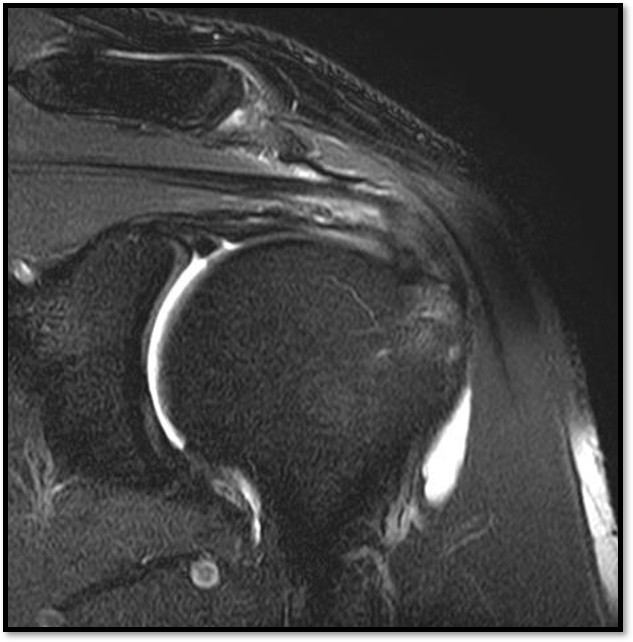

MRI를 검토해보았습니다. 확실히 회전근개 극상건에 부분파열이 있었습니다.

진단:

MRI: 극상건 관절면측 부분파열 (약 40%)

파열 양상: 가로 파열, 깔끔함

치료:

축소봉합술 (특수 드릴 + 콜라겐 봉합사)

재생주사 병행

재활 운동

결과:

12주 후 초음파: 봉합 부위 안정적 유지

6개월 후 테니스 복귀

MRI: 극상건 점액낭면측 부분파열 (약 35%)

인대 얇아짐 소견

16주 후 MRI: 인대 두께 증가 확인